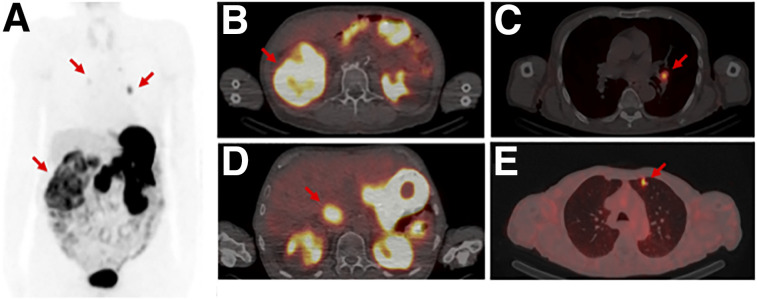

Patient 3 (an 80-y-old man) already had a diagnosis of ccRCC with lymph nodes metastases. The 99mTc-PHC-102 SPECT/CT scan showed physiologic uptake in the stomach and gut. Moreover, there was an inhomogeneous tracer accumulation in the right renal bed, assignable to the extended tumor mass. At the admission time point, a tumor mass was detectable in the vena cava. 99mTc-PHC-102 uptake inferiorly in the vena cava corresponded to the intravenous tumor mass. Interestingly, focal 99mTc-PHC-102 uptake was observed in the left upper lung lobe but was not previously described in CT reports (Fig. 4).

FIGURE 4.

Anterior SPECT (arrows indicate RCC and metastases) (A) and transverse SPECT/CT (B) scans obtained with 99mTc-PHC-102 in 80-y-old patient at 6-h time point. Primary large tumor mass (A and B) in right kidney (7.2 cm), arrow in B indicates RCC) was detectable because of high tracer uptake. Tumor thrombus in vena cava (B and C); indicated with an arrow in C), as well as metastatic lesions in lymph node (D) indicated with an arrow) and in lung (E), indicated with an arrow), were also visible 6 h after 99mTc-PHC-102 injection because of high tracer uptake.